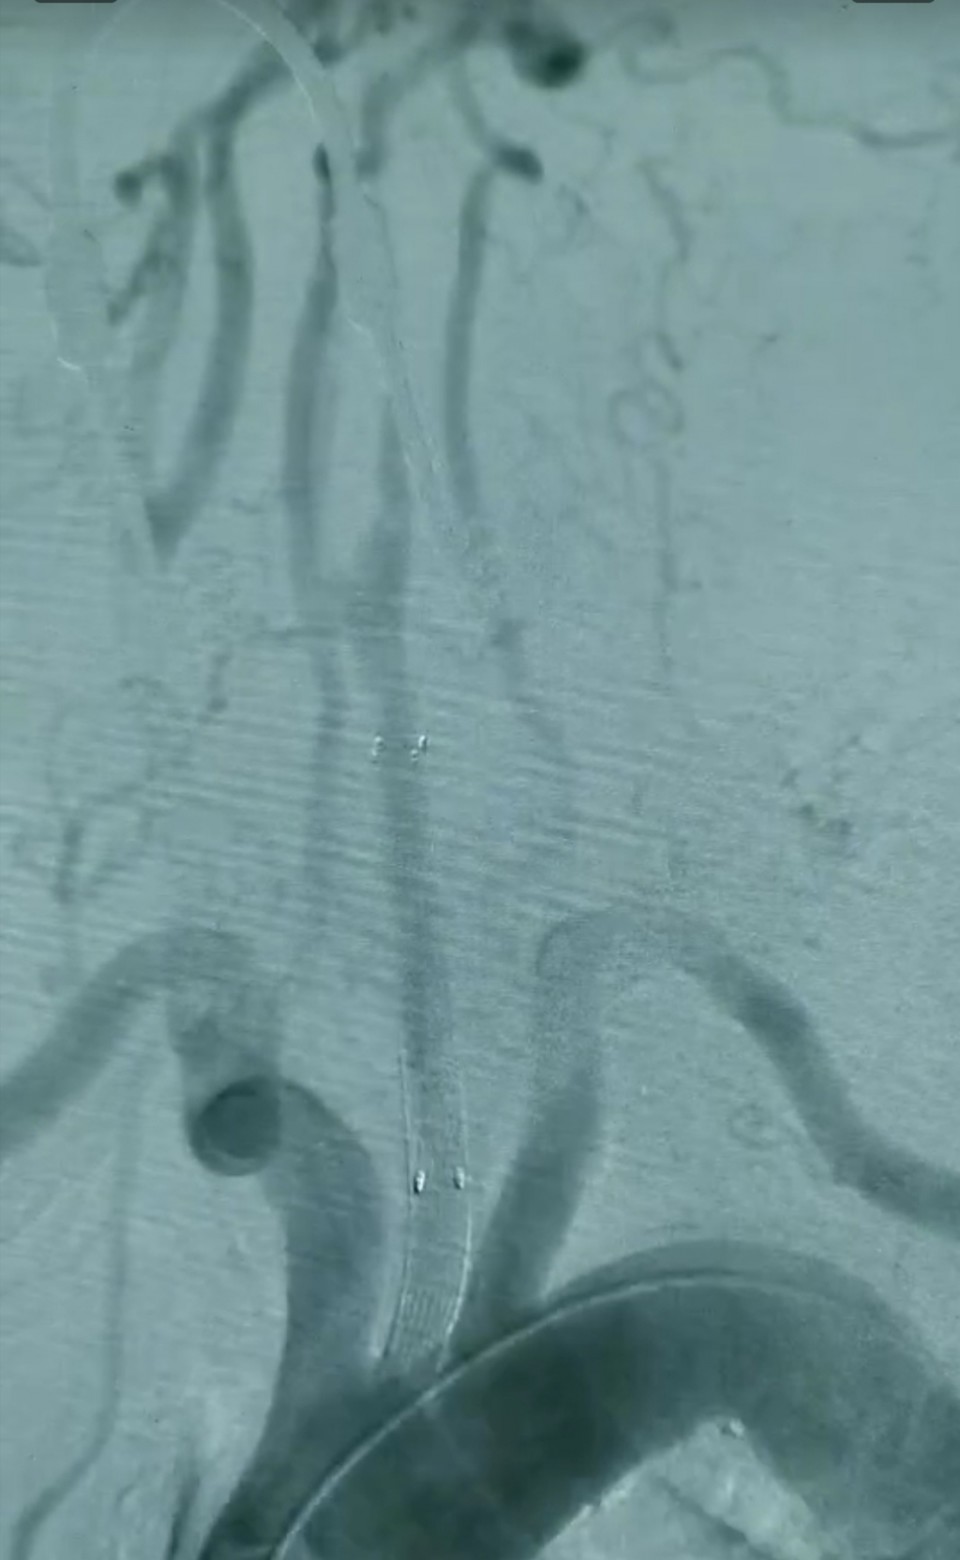

1月27号曹大爷入住我院血管甲状腺外科,入院后血管甲状腺外科给曹大爷做了头颈部的血管造影,进一步明确诊断及确定手术方案。经科室全体医生的讨论确定对曹大爷行左侧颈动脉内膜剥脱血管补片成型术+Fogarty取栓导管取栓+左侧颈总动脉覆膜支架植入术的治疗方案。该手术方式既解决了既往颈动脉完全闭塞不能进行微创外科治疗的问题,又降低了患者出现脑梗塞的几率;同时运用复合手术也增加了手术的安全性及降低了手术创伤性。目前省内还未有其它医院开展相似手术,国内也仅有少数几家医院才开展。

2月15号,在陈智勇主任的支持下,血甲状腺外科副主任医师张君为主刀,耗时约五个小时为曹大爷完成了这项手术。手术期间最大的困难是闭塞段颈总动脉真腔内开通障碍。术后患者恢复良好,主述头晕症状消失,一周后顺利出院。